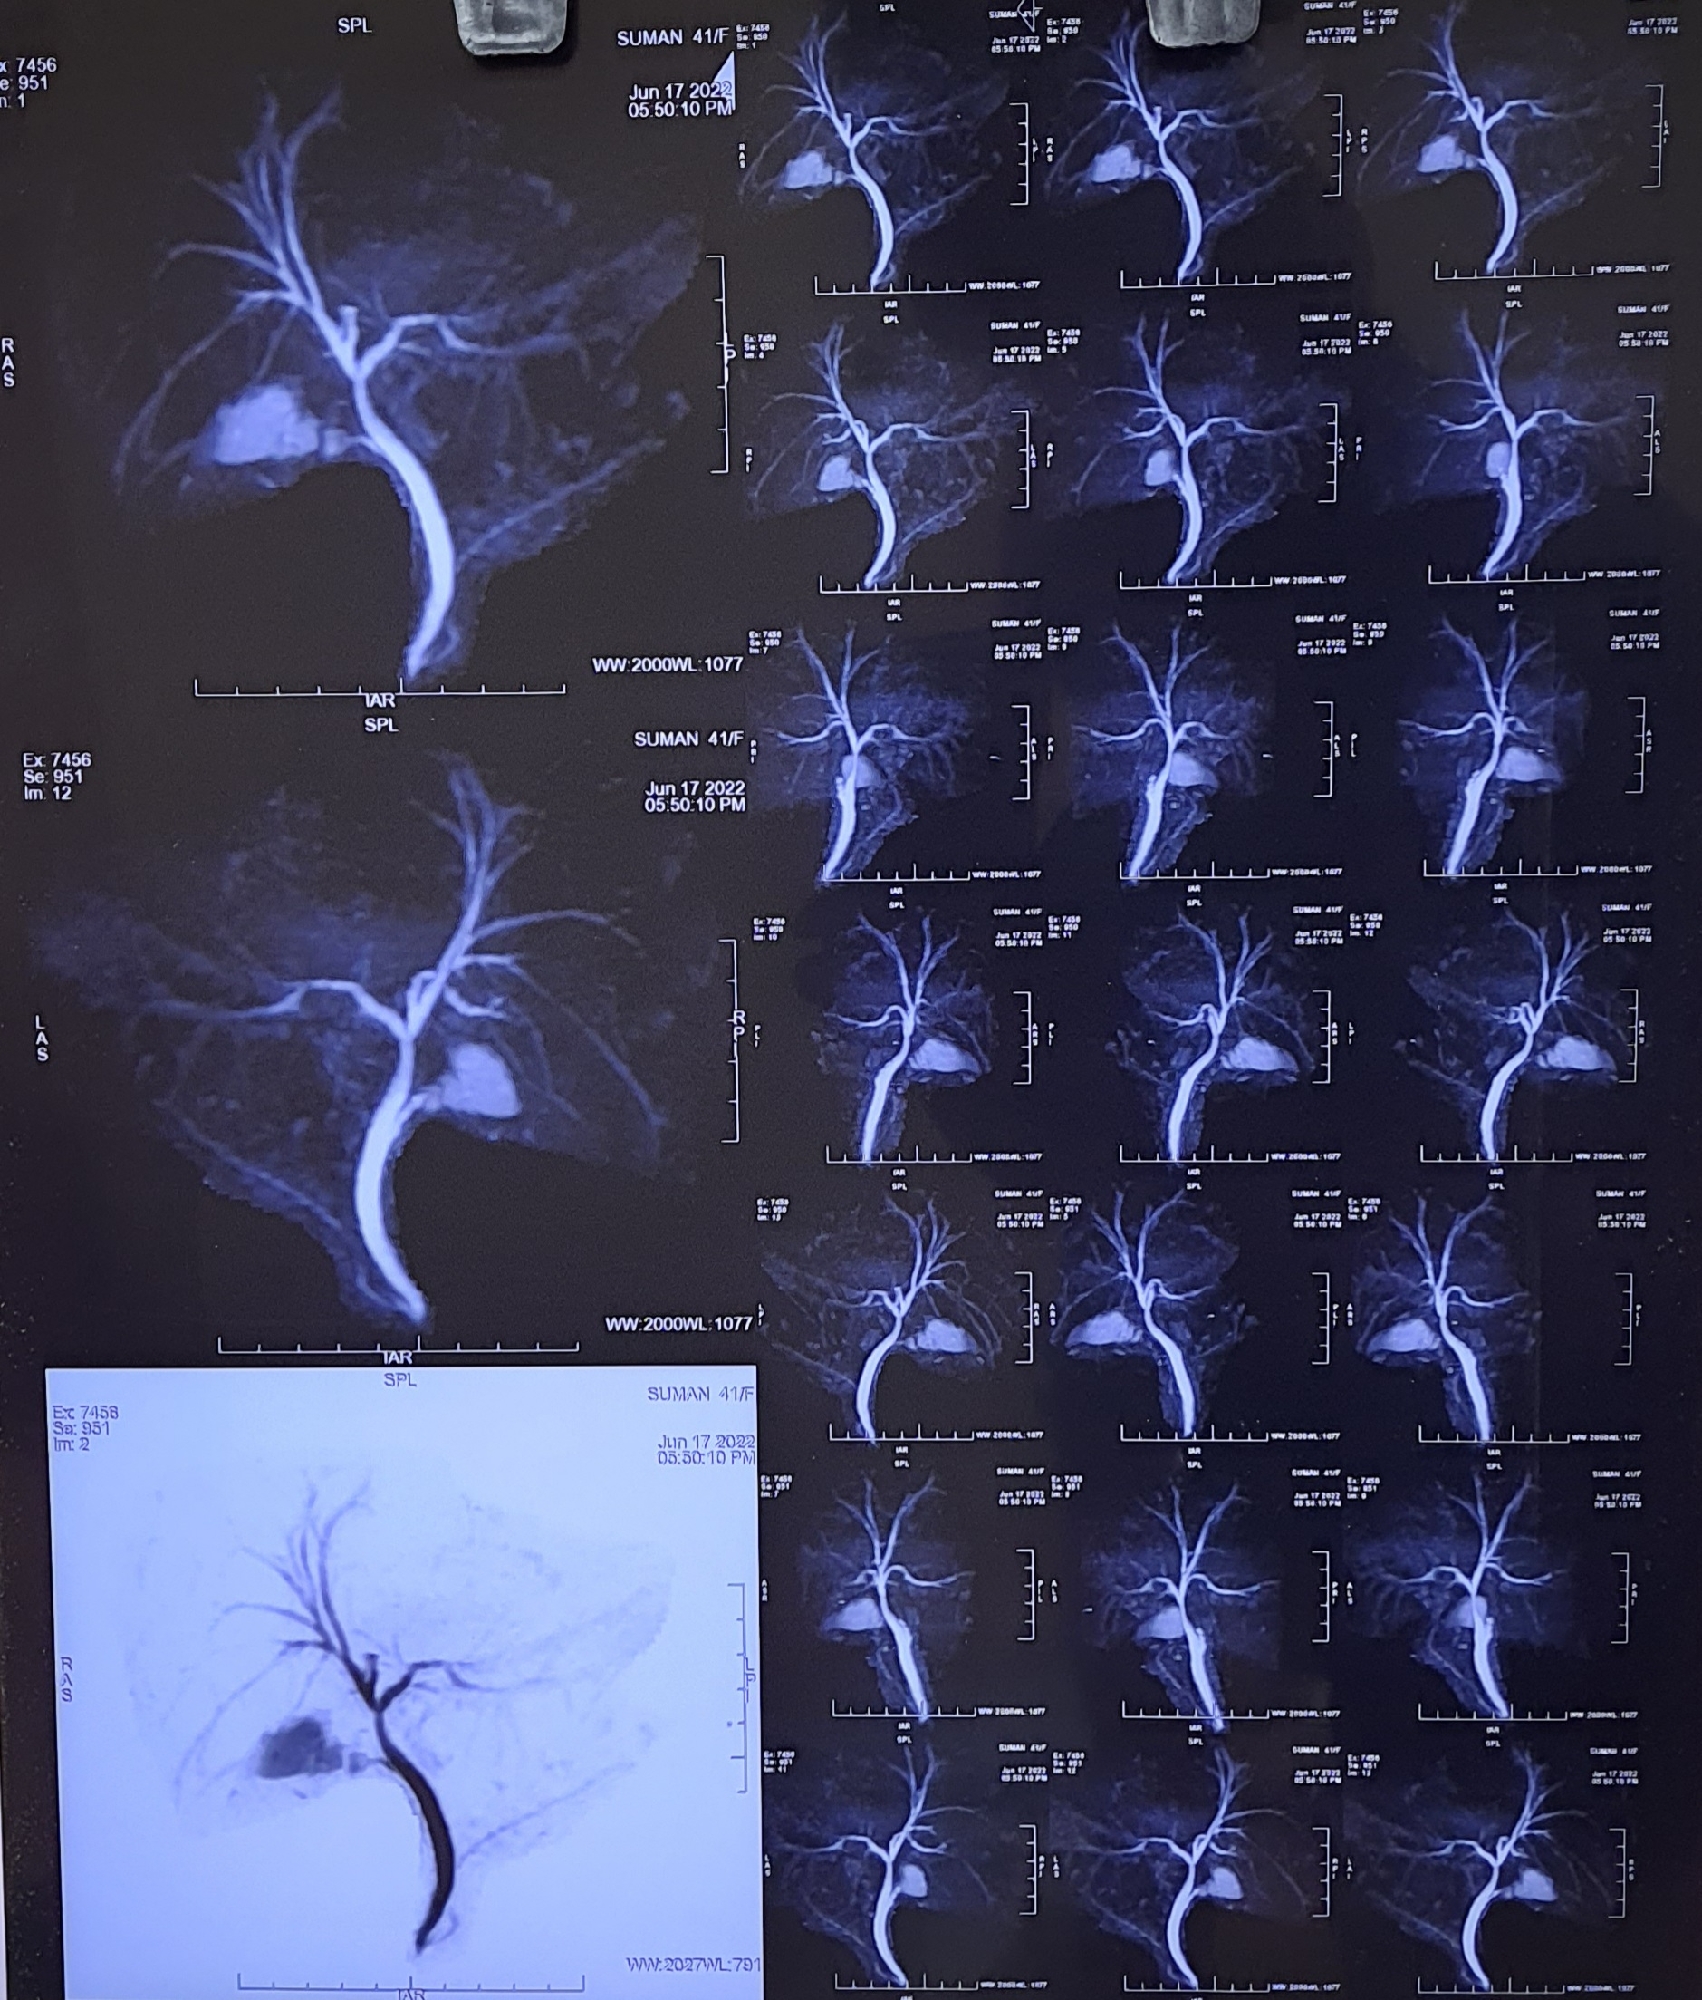

Biliary leak from the cystic duct stump after cholecystectomy. a PTC What Is A Cystic Duct Stump Leak 16 rows thirteen patients had significant bile leakage, three of which were from accessory ducts, in one the source could. other causes of leak include aberrant bile ducts, which drain from the liver into the gallbladder fossa, or failure of the cystic. postcholecystectomy leaks can occur from injury to the common bile duct, cystic duct stump, or. What Is A Cystic Duct Stump Leak.

Nonsubtracted image demonstrating occlusion of the cystic duct What Is A Cystic Duct Stump Leak if no drain was placed after surgery and imaging reveals a bile collection with suspicion of minor bdi (such as a. postcholecystectomy leaks can occur from injury to the common bile duct, cystic duct stump, or small ducts that drain from the. thirteen patients had significant bile leakage, three of which were from accessory ducts, in one. What Is A Cystic Duct Stump Leak.

Cystic duct remnant Coronal MRCP image showing cystic duct remnant

Cystic duct remnant Coronal MRCP image showing cystic duct remnant What Is A Cystic Duct Stump Leak postcholecystectomy leaks can occur from injury to the common bile duct, cystic duct stump, or small ducts that drain from the. if no drain was placed after surgery and imaging reveals a bile collection with suspicion of minor bdi (such as a. a cystic duct remnant is a term used when the size of the cystic duct. What Is A Cystic Duct Stump Leak.